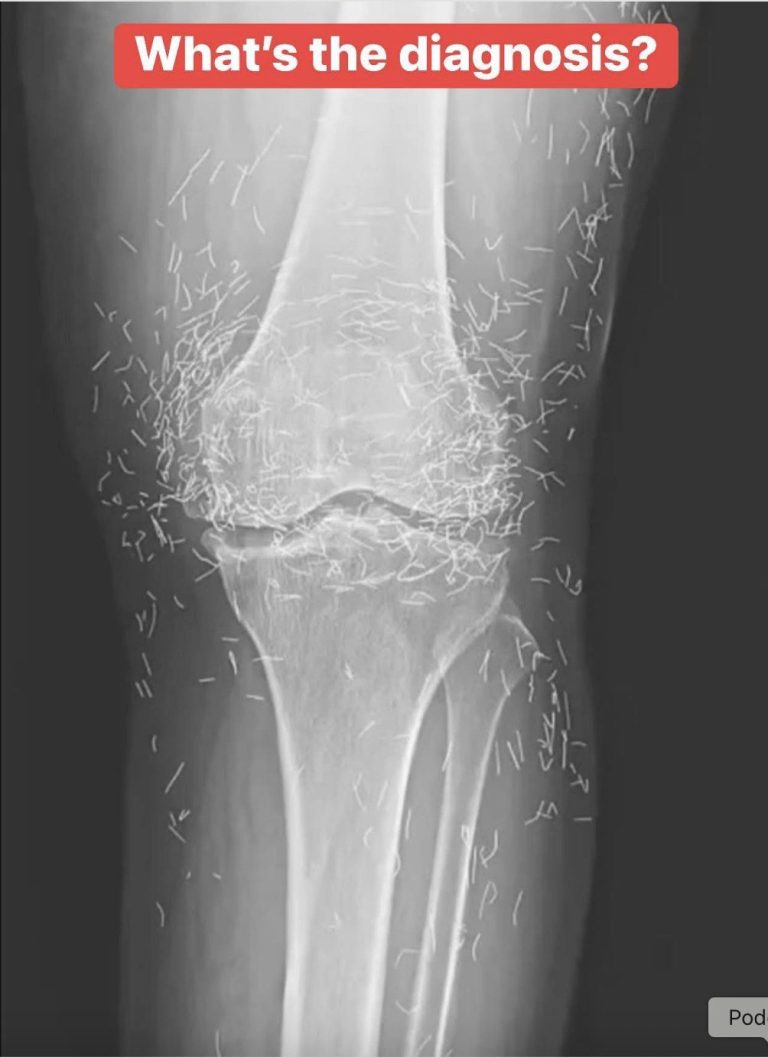

Medical experts believe the image shows a severe case of deep vein thrombosis (DVT) — a condition where a blood clot forms deep inside a vein, most commonly in the leg.

When blood flow is restricted for long periods — such as during extended immobility, dehydration, or compression — clots can form. If untreated, they can grow large enough to block circulation, causing intense swelling and color changes like the ones seen in the photo.

The bluish hue?

That’s blood struggling to circulate properly.

And it can become deadly.

If a clot breaks loose, it can travel to the lungs, causing a pulmonary embolism, which can be fatal within minutes.

The leg in the photo appears dramatically swollen from thigh to calf, with a bluish discoloration that many viewers described as “unnatural” or “terrifying.” Comment sections filled with guesses, jokes, and fear-driven assumptions.